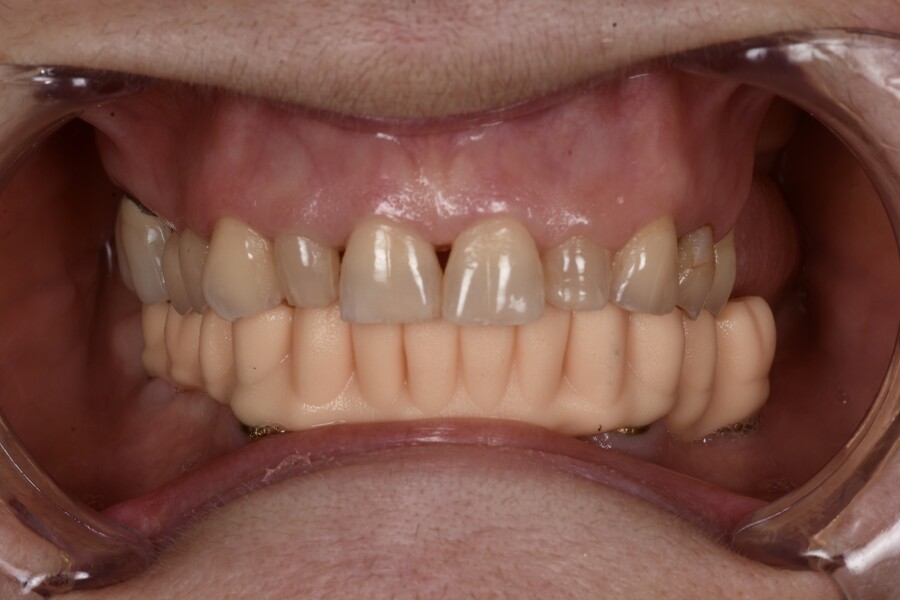

Fig. 8b: Delivery of the provisional restoration the day after the surgery.

Postoperative medication consisted of a seven-day course of amoxicillin–clavulanic acid (875/125 mg, twice daily), diclofenac (50 mg, up to three times daily as needed) and a chlorhexidine mouthrinse (two to three times daily). The patient was recalled the following day for delivery of the screw-retained PMMA provisional restoration, which showed excellent passive fit and acceptable occlusion (Figs. 8a & b).